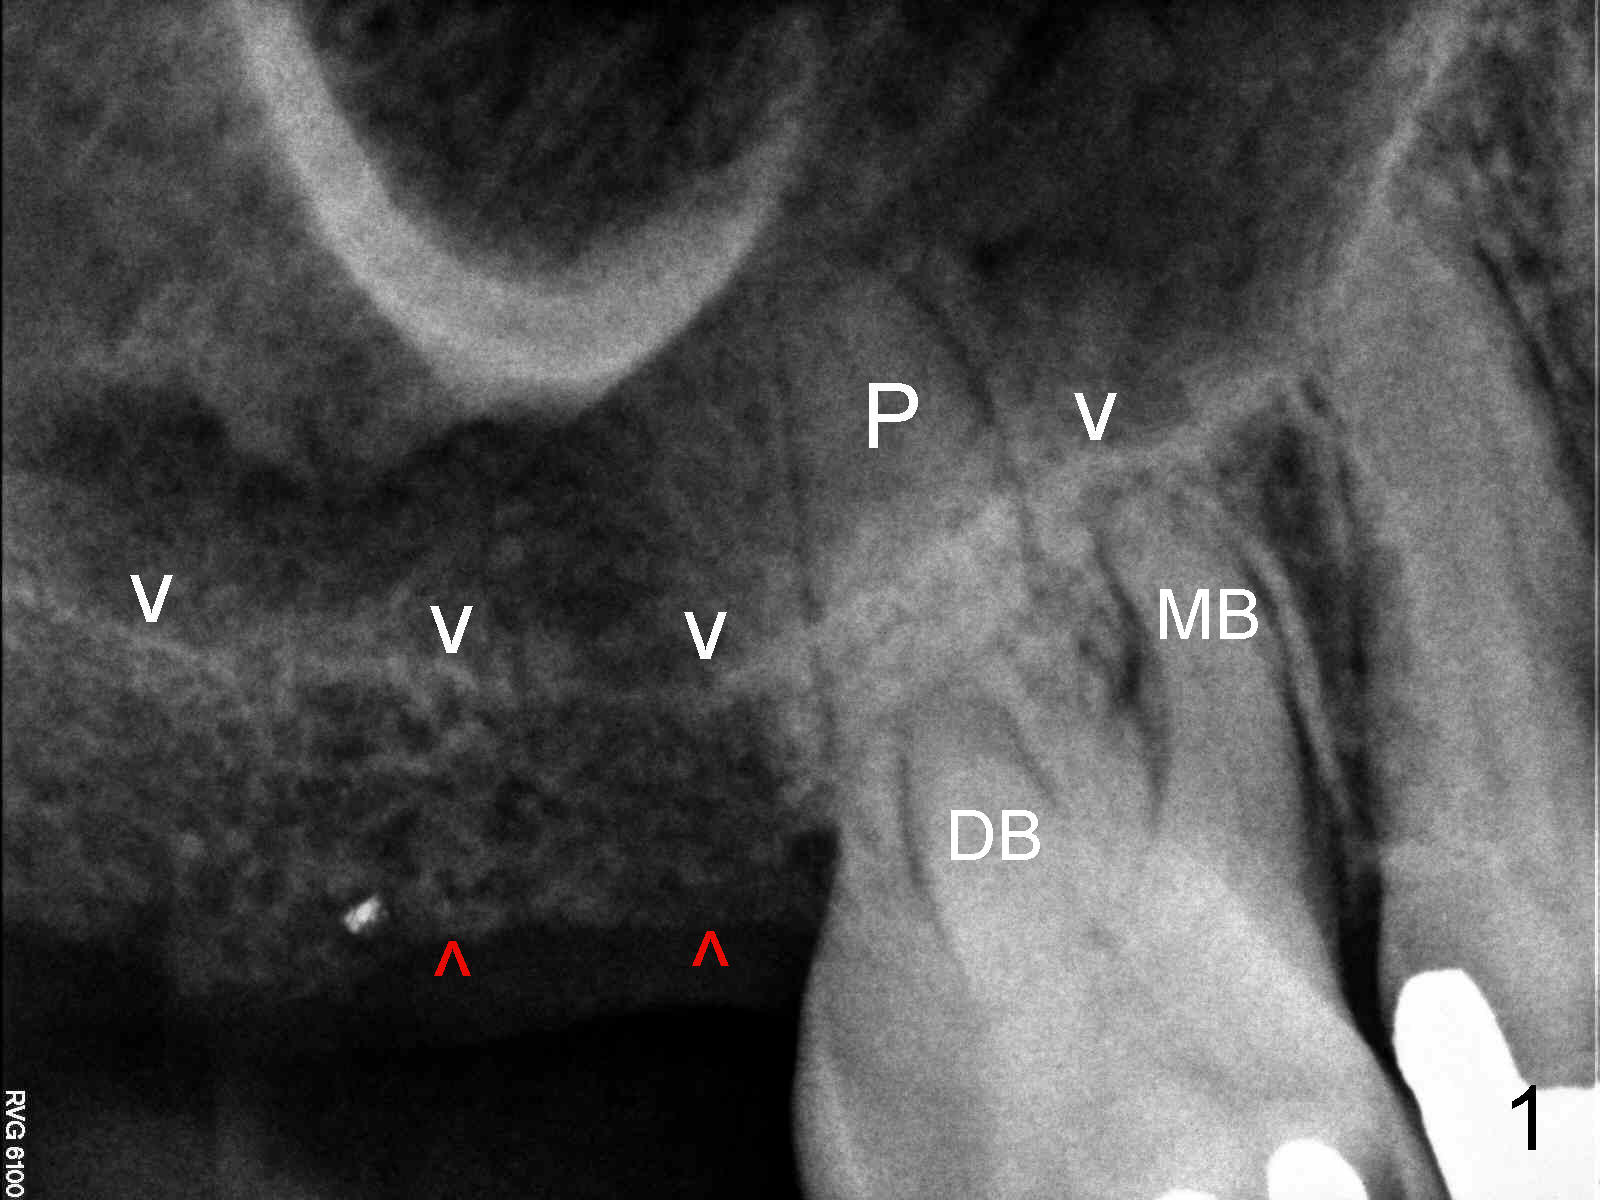

CBCT confirms the bone height (4.4 mm) (Fig.6).  Bone density is 200-400 Hounsfield units.  The best new is sufficient bone width (7 mm) buccolingually.